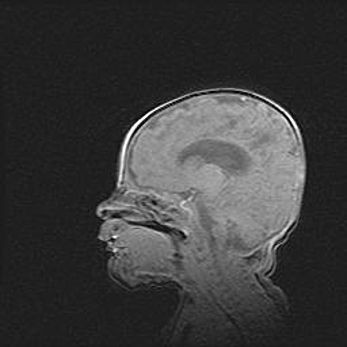

Церебральная ишемия II.

Возраст: 5 дней

Вес: 3400 г

Пол: женский

Окружность головы: 35 см

Срок гестации: 39 недель

Церебральная ишемия – это заболевание, характеризующееся недостаточностью (гипоксией) либо полным прекращением (аноксией) снабжения мозга кислородом по причине закупорки одного или нескольких сосудов. Это приводит к  что метаболическим расстройствам различной степени тяжести в тканях головного мозга, развитию коагуляционных некрозов и гибели нейронов.